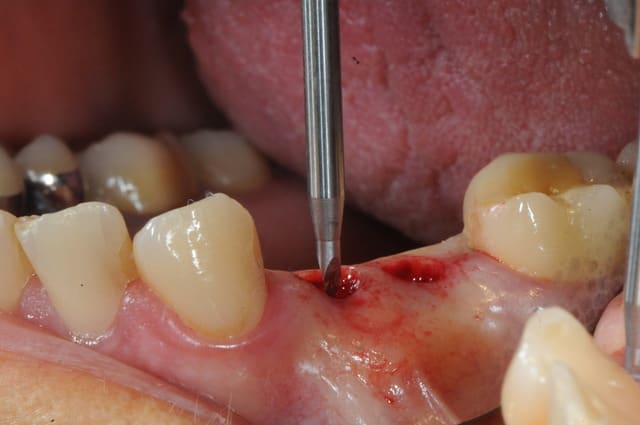

voici le dernier né de la gamme Axiom d'Anthogyr.

il a un corps conique et des spires beaucoup plus agressives pour augmenter la stabilité primaire.

son diamètre au niveau du col est légèrement réduit ce qui limite la compression crestal.

le cas que je vous présente date d'hier, il n'a rien d'extraordinaire, alors soyez indulgents, c'était juste pour le plaisir de partager ça avec vous.

2- foret pointeur (génial comme outil, bien mieux que la fraise boule)